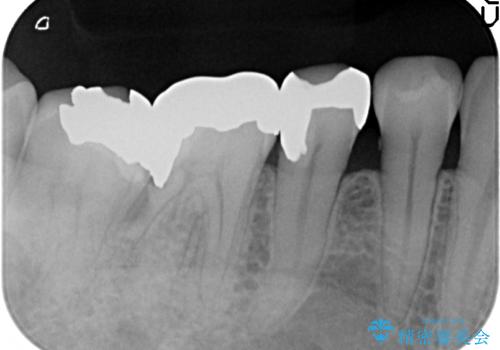

- 右下5番目の歯がしみるので診て欲しいといらっしゃった方の症例です。

古い銀歯及び虫歯を除去後、PGA(ゴールド)インレーによる修復を行いました。